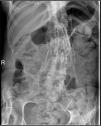

The patient was a 29-year-old woman, with a history of type 1A diabetes and primary amenorrhea secondary to cervical agenesis. At the age of 10 years, she was examined because she had developed a tumor in the cervical region, with no previous injury; she underwent a radiological study and bone biopsy that was compatible with myositis ossificans. Over the years, large ectopic ossifications developed in her shoulders, hips, knees, ankles and paravertebral muscles, which produced a marked secondary thoracolumbar scoliosis and a considerably generalized functional limitation. A plain radiology study of the affected areas showed the existence of exuberant bone bridges at different stages of maturation, that provoked the locking and ankylosing of a number of joints, including a knee (Fig. 1), the spine (Fig. 2) and a shoulder (Fig. 3). The patient was treated with bisphosphonates and calcium supplements with vitamin D for 5 years, while she was also being followed by the rehabilitation service; however, none of these measures was capable of arresting the course of the disease, which led to the physical disability of the patient.